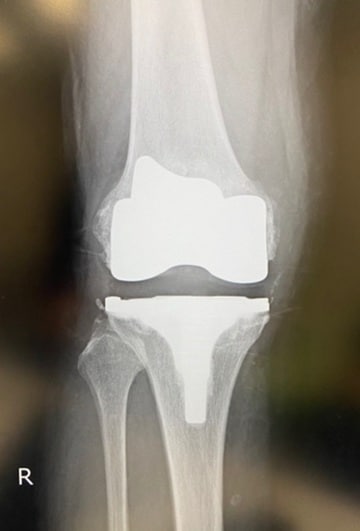

手術ではその点も考慮し、術後の速やかな回復をサポートするため、極力低侵襲の術式を採用することが大切です。下記のレントゲンを見ると分かるように、Aさんの手術は無事成功しました。

そこで手術では、人工膝関節に置換するとともに良性腫瘍もすべて除去。傷んだ軟骨やツノのように突起した骨軟骨種もすべて取り除き、すっかりきれいな状態になりました。

手術時間は80分。骨軟骨種もあったため、平均より若干長めでしたが、術後の回復は非常に好調でした。Aさんは1ひとり暮らしということもあり、希望通り13日間入院したあと、リハビリ病院へ転院しました。リハビリは、毎日30〜40分程度、それ以外の時間は自由に過すごしていたそうです。